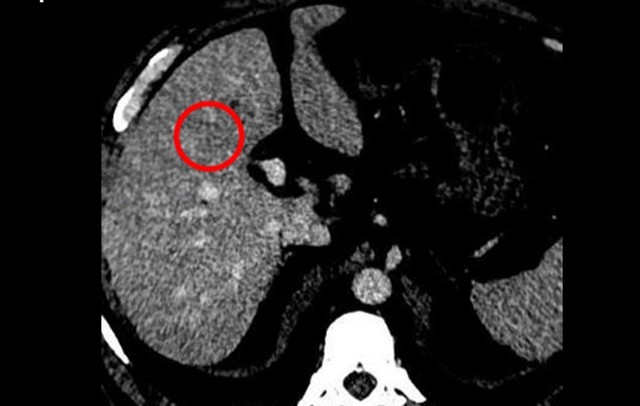

Kết quả chụp CT cho thấy gan xuất hiện khối tổn thương kích thước khoảng 22 x 24 mm cùng một số nốt nhỏ khác. Sinh thiết sau đó xác nhận ông mắc Ung thư gan giai đoạn sớm.